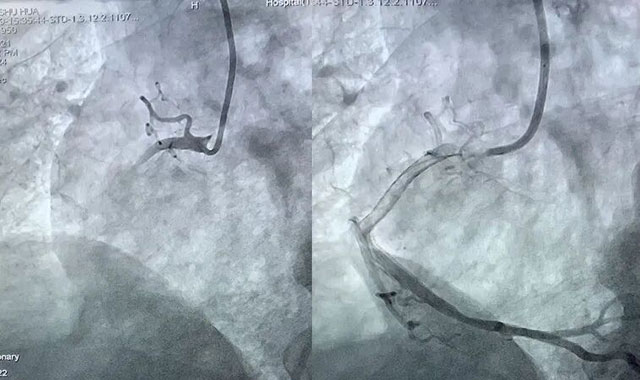

某基层医院医生在

专科联盟胸痛中心群里的紧急求助

消息刚发出,西南医科大学附属中医医院心血管内科CCU/NICU副主任江燕副教授立刻秒级回应,指导规范处置:“马上启动肝素抗凝、负荷剂量双联抗血小板,做好术前准备,我们这边已经激活导管室,30分钟内转过来,直接走胸痛中心绿色通道进导管室!”

按照指导

基层医院快速完成规范处置

及时转诊患者

经介入治疗后,患者成功脱险

并转回基层医院康复治疗